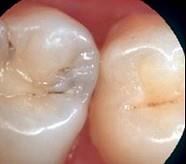

龋好发于牙齿的 ( )

- A.滞留区

A